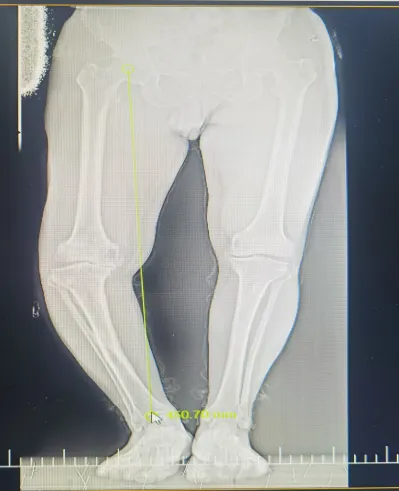

今年68岁的何爷爷是一位典型的右膝重度骨关节病患者。他右膝内翻畸形严重,行走时存在明显的跛行现象及O型腿,膝关节屈伸角度受限,下蹲困难,内侧胫骨平台缺损多,下肢力线极差,手术难度极大。多年来他饱受右膝疼痛的折磨,尤其在上下楼梯或长时间站立时,疼痛感更是明显加剧。